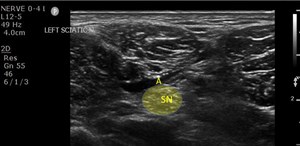

Popliteal Sciatic Nerve Block

A 55-year-old helmeted male with a past medical history of hypertension, hyperlipidemia, and hypothyroidism, presented with left ankle pain and left leg pain after hitting black ice and falling while ...